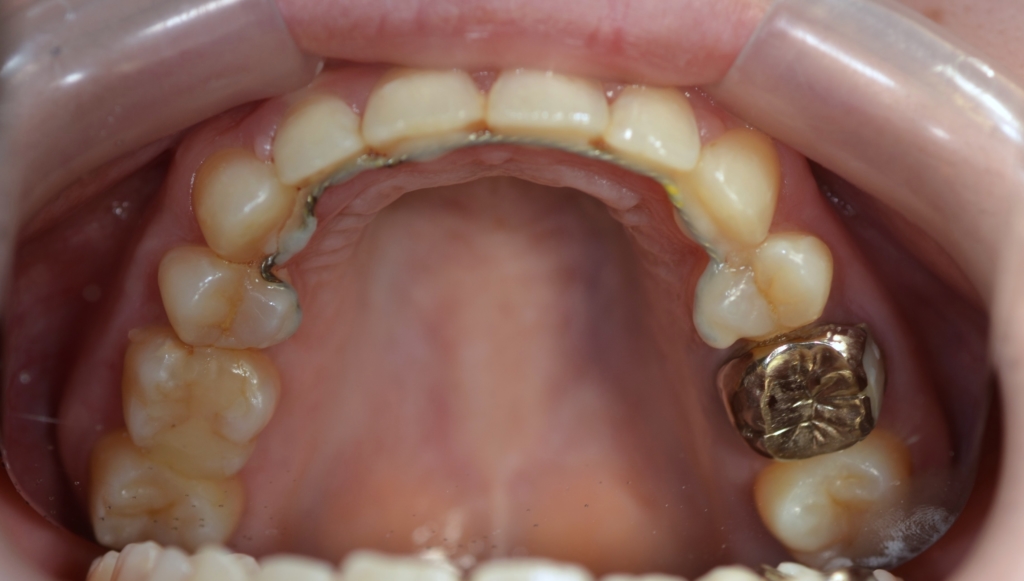

【治療装置】

マルチブラケットシステム(スタンダードtype)で矯正を開始。

アンカースクリュー

【治療開始】

まず、上の歯列だけに矯正装置を付けて、治療を開始します。